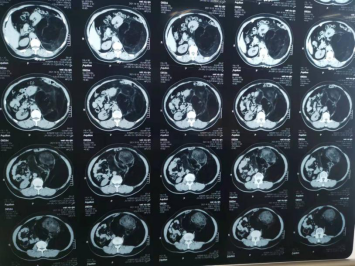

CT报告显示肿瘤直径18厘米

刘女士慕名来到哈医大二院普外科十病房,经过全面检查发现,在左侧腹膜后有一个直径长18厘米的肿瘤,已经将左肾挤压移位,压迫了腹主动脉。手术是唯一治疗方法。

王夫景介绍,肿瘤占据整个左侧腹腔,上界位于脾脏平面,下界达髂前上棘水平,前方与结肠紧贴,压迫了腹主动脉和左肾,导致左肾被推向剑突下方。由于肿瘤和腹主动脉关系密切,紧挨着大血管,导致手术难度变大,如果损伤腹主动脉,就下不了台,还要保证不能损伤肾脏以及结肠等脏器。